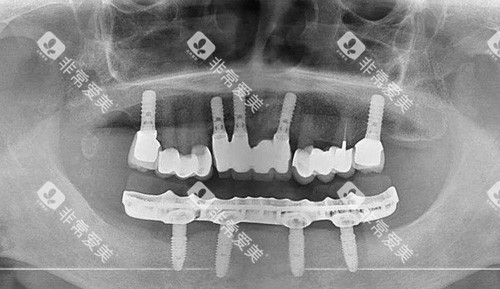

2. 全口种植牙:高端方案的"定制款"

"种4-6颗植体,上面搭个'固定牙桥'。"谢春医生解释。这种方案咀嚼效率更高,65岁的刘医师刚做完:"我现在啃甘蔗都不带怵的,比戴活动假牙舒服多了!"不过价格也更贵,全口种植普遍在15万-30万元起之间,还得看植体品牌——诺贝尔、ITI等进口品牌比国产的贵一倍。